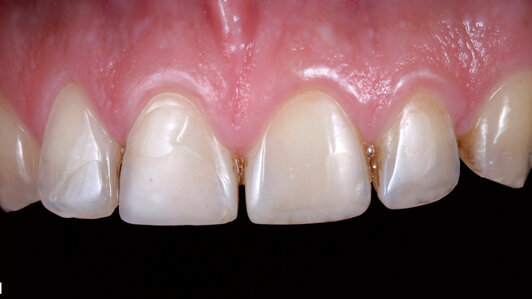

A male patient presented with abraded anterior teeth. The abrasion was caused by parafunctional habits, resulting in a loss of canine and anterior guidance. In addition, the aesthetic appearance was compromised (Fig. 1). As a large portion of healthy tooth structure was still present, we opted for a minimally-invasive treatment method using composite material. In addition, this method would allow us to restore the teeth with ceramic veneers at a later stage, should this become relevant.

Direct build-ups of composite restorations are suited, in selected cases, to re-establish the aesthetic properties and function of worn, aesthetically unpleasing anterior teeth. It is however important to select a composite that offers appropriate optical and mechanical properties. In the above clinical case, a group of anterior teeth were aesthetically restored with the Tetric N-Ceram nano-hybrid composite system (Fig. 9).

Fig. 9: Completed restoration of the aesthetic anterior region.